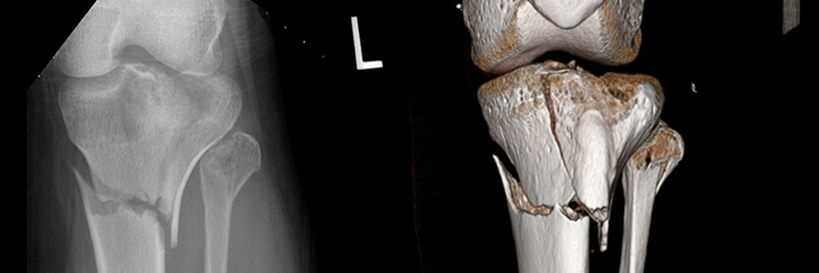

Musculoskeletal imaging uses medical images of bones, joints, and soft tissues to diagnose conditions. Our experts work to deliver timely and patient-oriented care to help with your evaluation and treatment.

Our Musculoskeletal Division offers a wide range of diagnostic services and image-guided procedures. We provide interpretation of all musculoskeletal studies using the latest technology, including:

• Conventional computed tomography (CT)